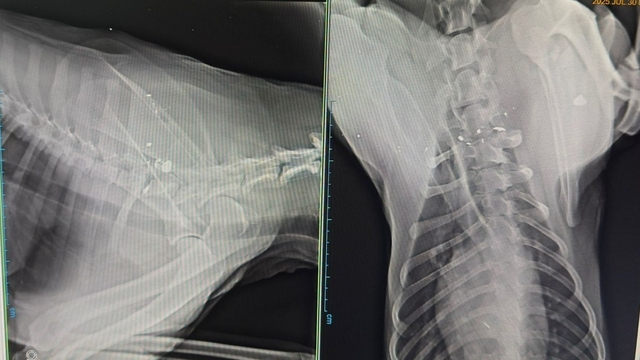

Olay, dün sabaha karşı Tosya Oto Sanayi Sitesi'nde meydana geldi. Kimliği henüz belirlenemeyen bir kişi, halı yıkama dükkanı işleten Atakan Oğuz'un evinin önünde beslediği 'Ateş' isimli köpeğe havalı tüfekle ateş etti. Tüfek sesi ve ardından gelen havlama sesleri üzerine dışarı çıkan Atakan Oğuz, köpeği Ateş'in yaralandığını gördü. İhbar üzerine olay yerine gelen polis ekipleri, güvenlik kamerasına yansıyan olayla ilgili inceleme başlattı. Oğuz ise köpeğini veterinerine götürdü. Burada yapılan tetkiklerde, merminin omuriliğe saplandığı ve köpeğin felç kaldığı tespit edildi. Şüpheli ise yakalanarak gözaltına alındı.

Atakan Oğuz, sıcak nedeniyle camları açık bırakarak yattıklarını ve gece yarısı tüfek sesi ile uyandıklarını belirterek, "Ardından köpeğin bağrışını duyduk zaten. Hemen sokağa indik. Bundan 5 yıl önce sünnet düğününde ,oğluma hayvan sevgisini aşılamak için sahiplendiğimiz Ateş isimli köpeğimizin yerde can çekiştiğini gördük. Hemen polisi aradık. Ondan sonra güvenlik kameralarından izledik. Birisi gelmiş, aşağı taraftan profesyonel bir havalı tüfekle Ateş'i nişan alarak vurmuş. Şahsı tanımıyorum, kim olduğunu bilmiyorum. Köpeğimizden ne istedi? Bizim köpeğimiz kimseye saldırmazdı. Burada tüm esnafın maskotuydu. Herkes onu çok severdi. Çocuklarımın oyun arkadaşıydı. Şikayetçi oldum. Görüntüleri polise de verdim. Şüpheli yakalandı ve şikayetim sonrası adli süreç başlatıldı" dedi.